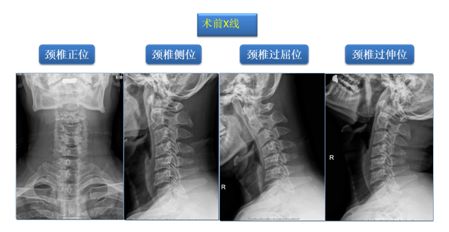

中年男性患者,40岁,该患者5年前出现颈痛伴双下肢乏力,未系统治疗。1年半前上症加重,伴头晕,双侧肩痛,颈肩部肌肉僵硬。为求系统诊疗来我科就诊。

考虑诊断:1.脊髓型颈椎病(C3-6椎间盘突出并相应椎管狭窄) 2.颈背胸部肌筋膜综合征

按照我科筋骨并重查体要求,我们发现患者不仅有脊髓损伤表现,触诊该患者颈肩部及胸背部时感受到多处筋膜及肌肉出现条索或者团块改变,颈肩部肌肉呈板结、僵直。显然患者颈椎处于筋骨失衡状态,这很可能是患者发展至脊髓型颈椎病的根本原因,也是患者自觉颈部酸痛、头晕昏沉的重要原因。

如果按照常规治疗选择,可能只是手术解除脊髓压迫,但我们在筋骨并治理念指导下,认为这位患者需同时接受理筋正骨手法及手术治疗,手法调节恢复筋骨平衡,手术解除脊髓神经压迫。

其后按计划实施我院特色术式:改良精准微创式颈椎椎板成形术(该技术是在梁徳主任指导下由江晓兵副教授改良),手术按照标准化流程下进行,术中耗时60分钟,出血量约50 ml。术后复查如下: